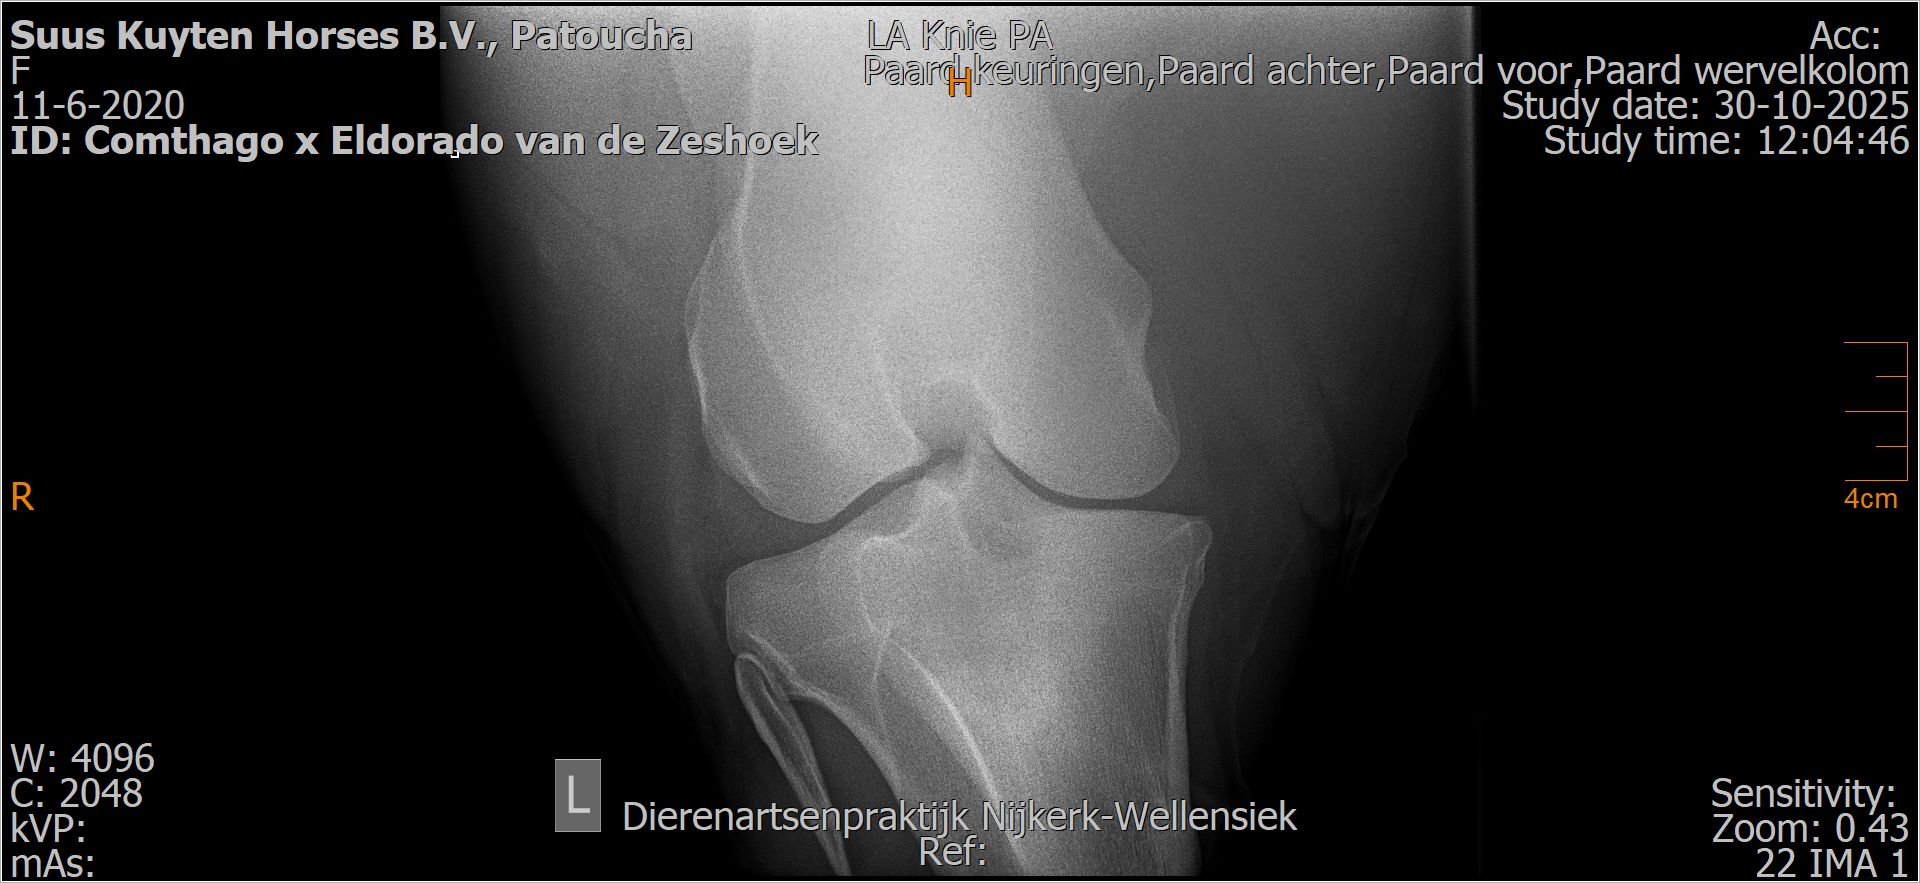

Patoucha

Leeftijd:

7

Röntgenfoto’s